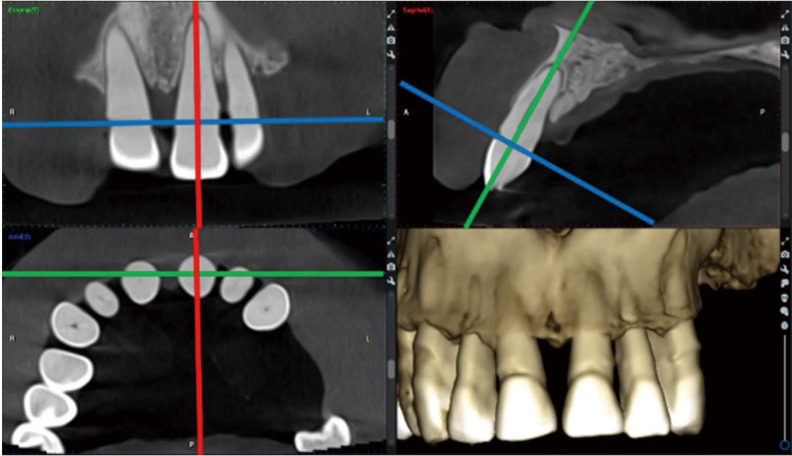

Purpose: This study was performed to introduce, evaluate, and compare various novel assessment protocols designed for straightforward, reliable, and reproducible measurement of alveolar bone levels. These protocols are intended for standardized periodontal assessment and follow-up, utilizing cone-beam computed tomography (CBCT) images and manipulation of Digital Imaging and Communications in Medicine (DICOM) viewer software.

Materials and methods: Two experienced oral and maxillofacial radiologists developed 5 distinct radiographic measurement protocols. These techniques were established to assess the alveolar bone level of a periodontally affected upper central incisor using a method that is consistently repeatable across observers. Two additional assessors, blinded to the details of the study, independently applied the protocols to retrieved DICOM files that met the eligibility criteria. A scoring system with 3 subscores was created and used to compare the protocols.